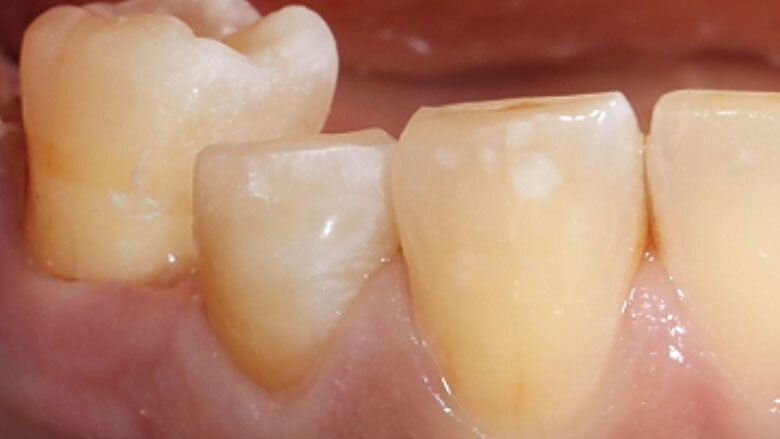

Fig. 13. Vista oclusal de la endocorona colocada de forma totalmente adhesiva.

Fig. 14. Resultado: integración altamente estética de la restauración durante la revisión al cabo de seis meses.